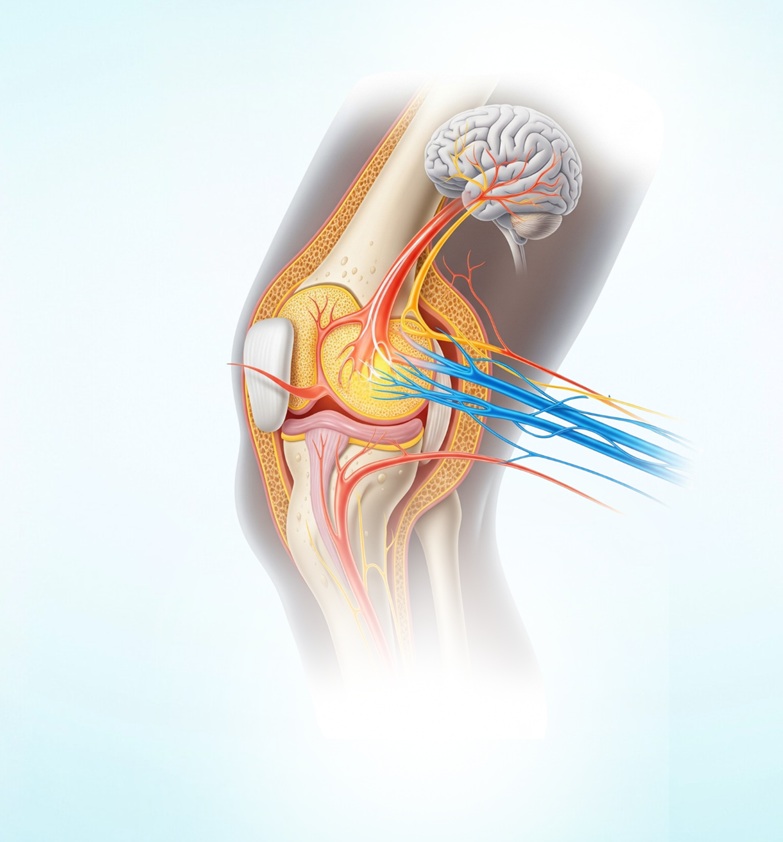

Ostizeel™ is a synergistic formulation of Palmitoylethanolamide (PEA) and Cucumis sativus extract, designed to act on both nociceptive and neuropathic pain pathways. These two mechanisms are central to the development and persistence of osteoarthritis pain. Nociceptive pain arises from joint tissue damage and inflammation, while neuropathic pain results from nerve sensitization and neuroinflammation. By addressing both, Ostizeel™ delivers targeted and lasting relief.

Ostizeel™ has been scientifically formulated to modulate critical molecular mechanisms that contribute to osteoarthritis progression. It targets mast cells, TRPV1 receptors, PPAR-α, and microglial cells all of which play key roles in pain transmission and inflammation. The result is a dual-action response that reduces both inflammatory and neuropathic pain.

In addition to its analgesic action, Ostizeel™ offers chondroprotective benefits by inhibiting matrix metalloproteinases (MMPs) enzymes responsible for cartilage breakdown. The formulation also downregulates major inflammatory biomarkers such as TNF-α, IL-6, IL-1β, and NF-κB, helping reduce joint inflammation and slow disease progression.